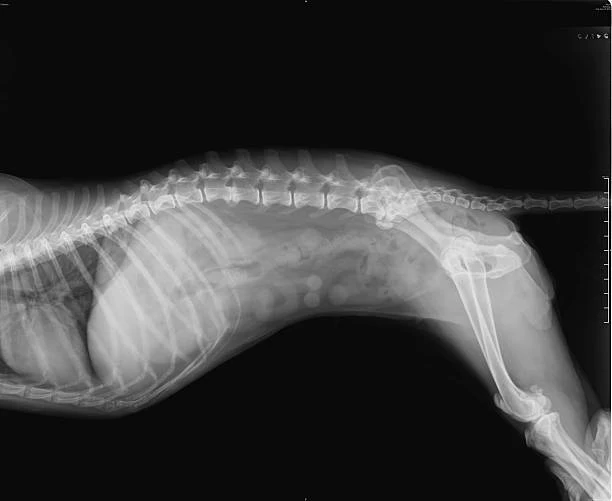

O raio x é um exame de imagem não invasivo que permite visualizar estruturas internas do corpo do animal, como ossos, órgãos e tecidos moles.

Ele é fundamental para identificar fraturas, tumores, obstruções, problemas cardíacos, entre outras condições que podem afetar a saúde do seu pet.